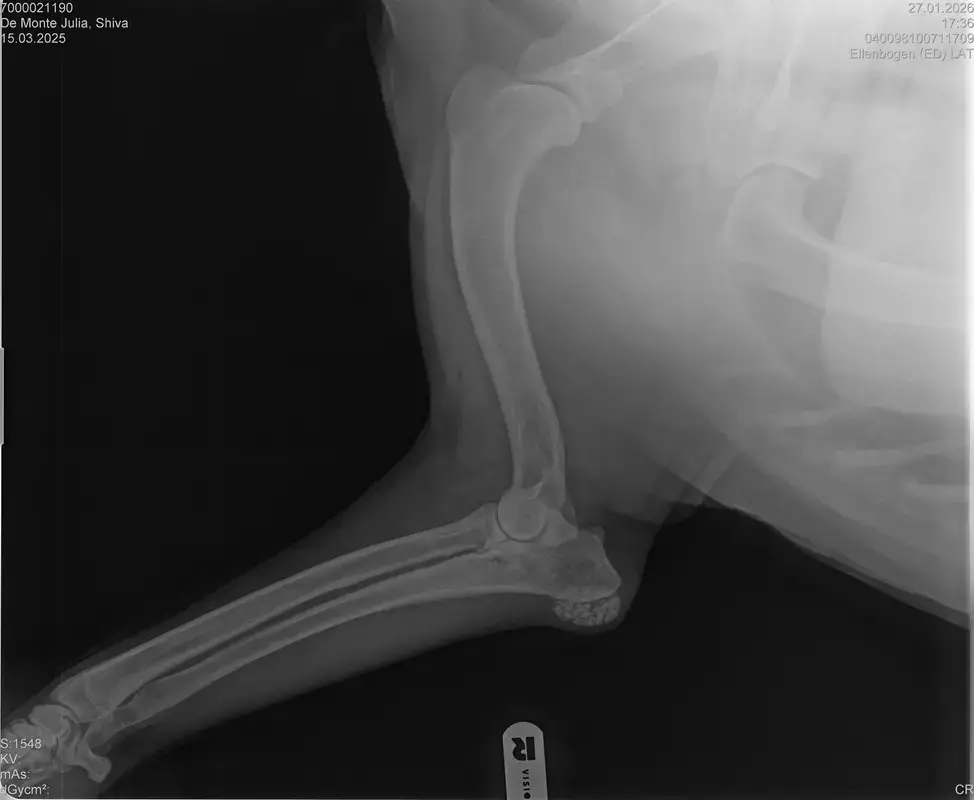

Vorige Woche kam mir Shiva verändert vor, nicht der aufgeweckte Spaßvogel der er sonst ist. Ich dacht vl ist er im Garten iwie blöd ausgerutscht weil unser gesamtes Grundstück über Wochen von einer dicken Eisschicht überzogen war. Er lag viel rum, zuviel da er doch zu den Wirbelwinden unter den Junghunden gehört. Er quetschte sich zum schlafen an mich ran, was auch untypisch für ihn ist. Er ist immer so „iiiii fass mich nicht an“. Ich nehms ihn nicht böse er ist nicht der große Kuschler :D Hat er wohl von mir :D :D aber er pickte nur an mir dran, ruhen ohne Körperkontakt war nicht möglich. Fand ich schön aber da ich wusste dass es nicht Shiva ist machte ich mir schon Sorgen… Am nächsten Tag wollte ich ihn bürsten alles war wie immer, er legte sich hin und sah mir zu wie ich einen Fellberg stapelte. Bei seinen Hinterpfoten hörte ich auf und dachte mir ich fühl mal vorsichtig.. Plötzlich knurrte er mich an vor Schreck weil ich damit überhaupt nicht gerechnet hatte zuckte ich reflexartig zurück (was lt Trainerin ein Fehler war)… Aber ich hab nicht mit einer derartigen Reaktion gerechnet, Shiva hatte schon 2 kleine Verletzungen die ich ohne Probleme verarzten konnte. Am nächsten Tag gings ab zum TA. Mit Maulkorb da ich nichts riskieren wollte. Nach der Untersuchung wo er auch mehrmals knurrte gings ab zum röntgen. Und das riss mir den Boden unter den Füßen weg. Dann die Aussage von der TA „ich weiß sie wollen einen gesunden jungen Hund aber das ist Shiva leider nicht“. Was jetzt? Er ist so ein aufgewecktes Kerlchen, absolute Lieblingsbeschäftigung ist Parcour. Er macht es so gern, ja auch UO und Suchspiele aber das leuchten in seinen Augen wenn wir Geräte machen :( (er macht noch keine schweren Geräte wie A Tafeln oder springen… Aber die seichten macht er mit absoluter Leidenschaft.. Ruhe halten über mehrere Monate… nur langsames gehen oder schnüffeln.. puh ich weiß nicht wie ich ihm verbieten soll zu rennen und zu toben… Vl habt ihr Tipps für mich. Im Anhang der Befund und ein paar Bilder vom kleinen Wirbelwind. <3

• Naja die Diagnose kommt von einem „Facharzt“, lt TA war ihrerseits alles i.O. Sie wollte noch sicher gehen und die Bilder zur weiteren Befundung einschicken und das kam dabei raus. Und der Therapievorschlag beläuft sich auf Ruhe, Ruhe und noch mehr Ruhe. Und einer Schmertherapie von Gabapentin 800mg 1/2 Tablette 2x tgl, Carprodyl 120mg 1 1/2 Tabletten 1x tgl und TamaCan CBD Tropfen 10-15 Tropfen 2x tgl. 1x in der Woche soll ich telefonisch Auskunft geben wie es Shiva geht. Das ganze mal für 14 Tage. Sie meinte noch sie hat viele Junghunde die ein Leben lang Schmerzmittel nehmem müssten. Die Röhrenknochenentzündung heilt in der Regel von selber der Rest gehört beobachtet… Ich weiß im Moment auch nocht so recht.. Er tut mir nur wahnsinnig leid mit sovielen Diagnosen und für mich war erstmal vorrangig ihn schmerzfrei zu bekommen. Das ist er inzwischen und versteht die Welt nicht mehr warum er nicht wie sonst spielen und arbeiten darf. Im Anhang noch Röntgenbilder falls sich jemand damit auskennt bzw Interesse hat..

• Ok, die Röntgenbilder sind aber auch extrem schlecht.

Panostitis ist idR sehr schmerzhaft, aber nicht unüblich und heilt in der Regel von alleine aus, wichtig dabei ist schonen und Entzündungshemmer zu geben, damit das nicht chronisch wird. Ich denke, dass die Akut bemerkbaren Schmerzen hauptsächlich davon kommen. Also da passt die Empfehlung deiner TÄ für's Erste auf jeden Fall.

Wenn dieser Panostitis-schub rum ist, würde ich dem Rest nochmal nachgehen. Man kann bei Dr. Tellhelm ( SV Gutachter) ein privatgutachten in Auftrag geben, das kostet um die 100€. Da kriegst du halt ne konkrete Einstufung und nicht "verdacht auf" und "könnte hiermit ODER damit in Verbindung stehen", etc.

Ich denke aber, dass du für ein Gutachten von Tellhelm nochmal neu röntgen lassen musst, ich finde, dass das Bild der Hüfte (HD und LÜW wird da beurteilt) und die Draufsicht auf die Ellenbogen (nötig zur Beurteilung von ED) unterirdisch sind!